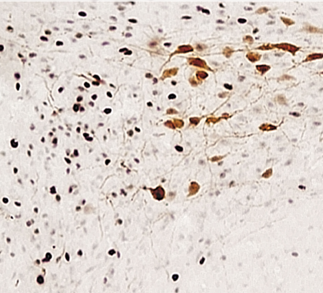

El sistema de regulación de la osmolalidad hídrica en el organismo humano se apoya en una red de neuronas llamadas «osmorreceptores» centrales, que incluyen las neuronas magnocelulares responsables de expresar la vasopresina (AVP), también conocida como hormona antidiurética. Estas neuronas magnocelulares tienen una función crítica en la percepción y respuesta a los cambios en la osmolalidad circulante, lo que se traduce en una regulación precisa del equilibrio de agua y solutos en el organismo.

La percepción de la osmolalidad circulante se lleva a cabo mediante conductos catiónicos activados por estiramiento no selectivos. Estos conductos se encuentran en la membrana celular de los osmorreceptores y son particularmente sensibles a los cambios en la presión osmótica del fluido extracelular, es decir, cómo de concentrados o diluidos están los solutos en la sangre.